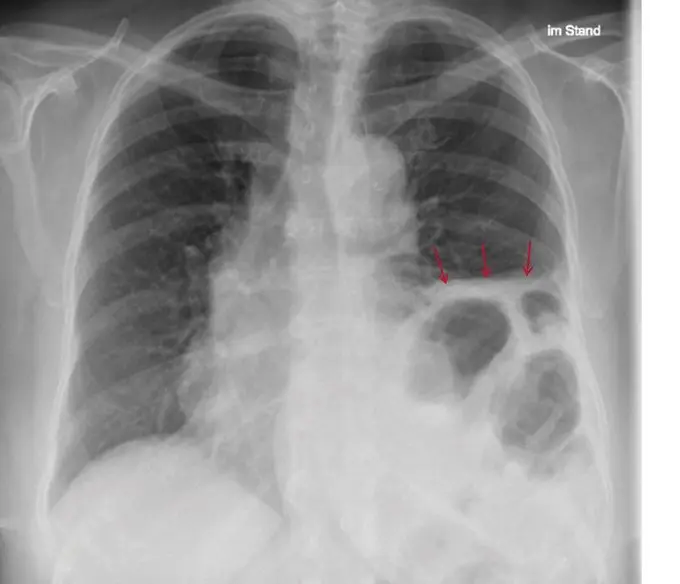

- Röntgenaufnahme des Brustkorbs: Eine Röntgenaufnahme des Brustkorbs zeigt, ob das Zwerchfell auf einer oder beiden Seiten höher steht als normal.